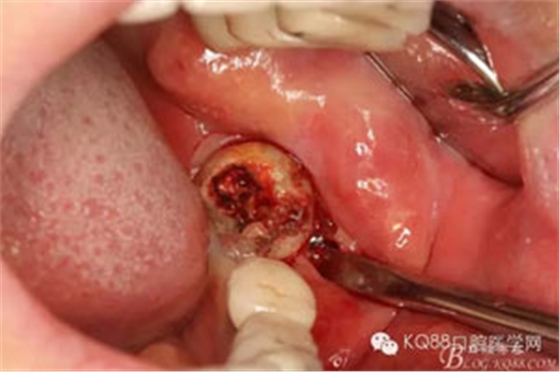

圖7.普通丫挺挺出38牙齒